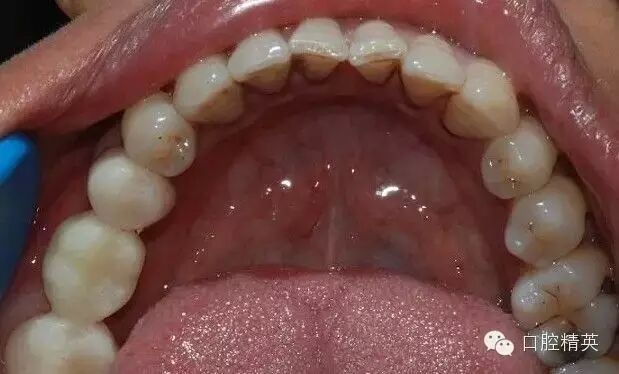

臨時冠頜面觀

模型照片